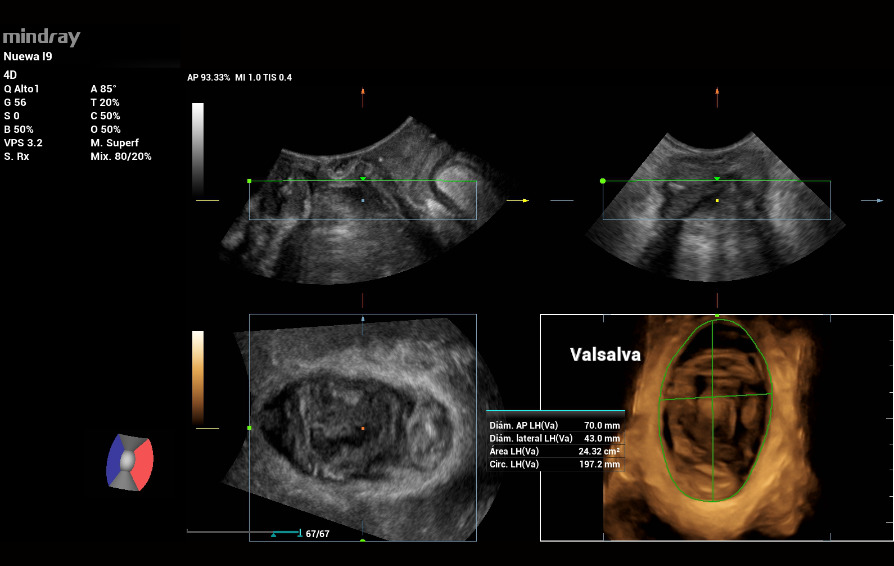

In the 3D/4D scanning, the Levator ani muscle status is intact, evaluated by the multi-slice tool iPage in contraction and the measures were: Left GAP 17mm, Right GAP 19mm (Figure 4). The Levator hiatal area in Valsalva was 24cm2 within normal values. (Figure 5)

In the 3D/4D exploration mode, the Levator ani muscle was observed intact. In the tomographic or multi-slice ultrasound evaluation (iPage) during contraction, the following measurements were obtained: left GAP 24mm, right GAP 25mm (Figure 9. a). The area of the Levator hiatus during Valsalva was 30cm2 with moderate ballooning (Figure 9. b).